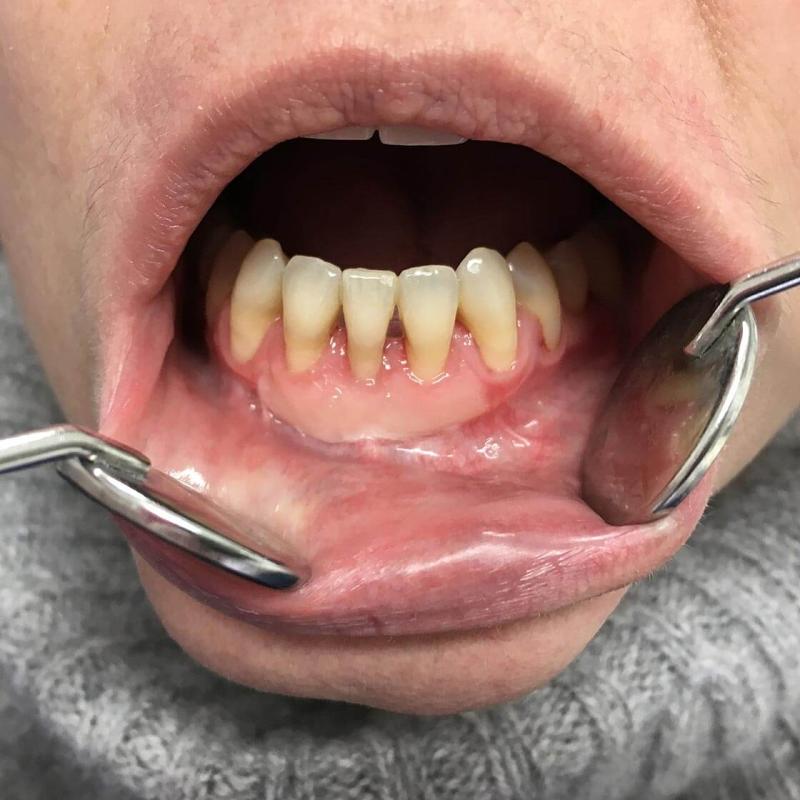

La parodontologia controlla il benessere delle strutture portanti dei denti (gengive e osso di sostegno) cercando di prevenire o curare la piorrea che nella popolazione adulta è la più frequente causa di perdita dei denti.

Oggi più che mai viene richiesta la copertura di esposizioni radicolari mediante la chirurgia estetica mucogengivale. Inoltre con la cura della piorrea si mantiene in buono stato la salute generale del paziente prevenendo complicanze cardiovascolari e diabetiche.